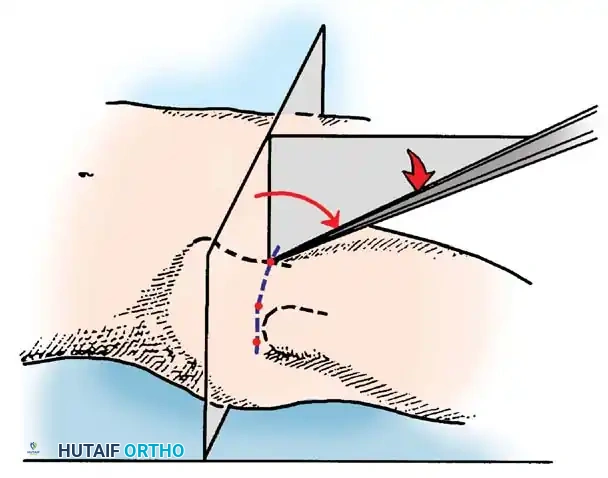

This is typically the first portal established, as it lies within the primary "safe zone."

- Location: Positioned just superior and anterior to the tip of the greater trochanter.

- Trajectory: An 18-gauge spinal needle is advanced toward the femoral head along a line 45 degrees medial and 45 degrees proximal.

- Anatomy Traversed: Penetrates the gluteus medius muscle.

- Structures at Risk: The superior gluteal nerve traverses approximately 4.4 cm cephalad to this portal. Staying close to the trochanteric tip ensures safety.

- Initial Access: Establish the anterolateral portal first using a 6-inch, 17-gauge or 18-gauge spinal needle under continuous fluoroscopic guidance.

- Capsular Penetration: If excessive resistance is met during needle placement, redirect it under fluoroscopic control, aiming slightly more parallel to the femoral head and away from the cartilaginous edge of the acetabulum to prevent iatrogenic labral puncture.

- Venting the Joint: Distend the joint with 30 to 50 mL of sterile saline. A reverse flow of fluid signals successful entrance into the intra-articular space and breaks the vacuum seal, allowing the joint to distract fully.

- Cannula Insertion: Pass a flexible nitinol guidewire through the needle, withdraw the needle, and pass the cannulated obturator and sheath assembly over the wire. Never use excessive force, which could score the femoral head.